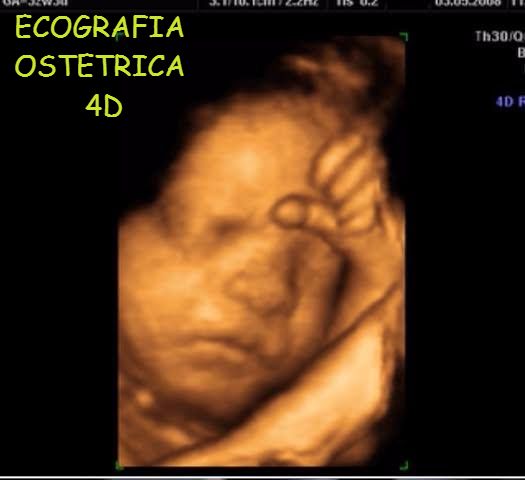

Si interessa inoltre di ecografia ostetrica di 1 e 2 livello, ottenendo l’accreditamento per la pratica della Translucenza Nucale Fetale dal 2008, e di ecografia mammaria.

• Ecografia ostetrica